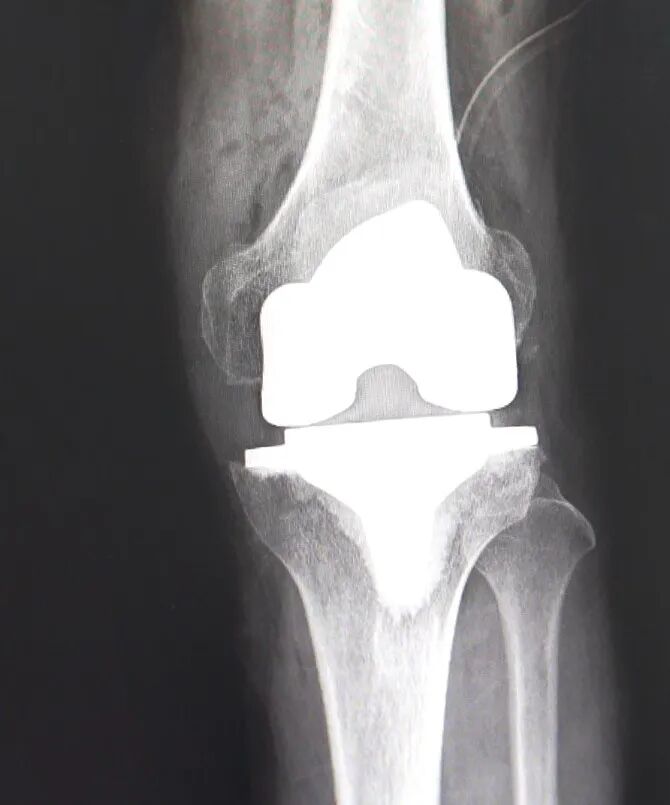

△手术后

王益民说:“经过一些实践以后,我们发现机器人辅助全膝关节置换,误差在一个毫米以内,这样就能做到很精准的关节假体的植入。”

在对患者耐心细致地解释手术方式后,患者采纳了医生的建议。术中,医生借助机器人辅助技术,开展精准截骨,调试安装好假体后,一台复杂的全膝关节置换手术就这样轻松完成。

李先生术后不久就能下地行走了,对此他特别高兴,“通过这次手术,关节已经恢复正常了,已经拉直了,走路没有感觉疼痛了。”李先生说。

据悉,这是常州市第一人民医院成功开展的全市首例机器人辅助下膝关节置换手术,在机器人的参与下,可实现复杂手术安全化、精准化、微创化、降低并发症发生的可能性,术后功能恢复、康复也会更快,让患者全方位受益。